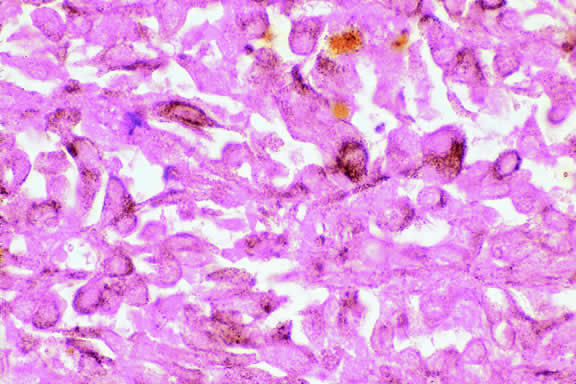

Histopathologically, melanocytomas are composed of cells that have abundant quantities of maximally pigmented cytoplasm that often obscures nuclear details, making microscopic assessment impossible11 (see Fig. 5). Bleached sections, which are a requisite for examination, show that the cells have bland nuclei and a low nuclear-to-cytoplasmic ratio (Fig. 6). Nucleoli usually are inconspicuous, but there are exceptions to the rule. Electron microscopic studies also have revealed a second population of spindle cells.15,24 Melanocytoma cells resemble the benign melanocytes found in the uvea of patients with ocular melanocytosis.

Fig. 6. Melanocytoma, depigmented section. Bleaching of melanin pigment discloses cells with bland nuclei and low nuclear-to-cytoplasmic ratio consistent with benign magnocellular nevus. (Bleach, × 250.)